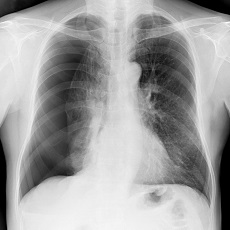

A collapsed lung happens when air enters the pleural space, the area between the lung and the chest wall. If it is a total collapse, it is called pneumothorax. If only part of the lung is affected, it is called atelectasis.

A chest x-ray can tell if you have it. Treatment depends on the underlying cause.